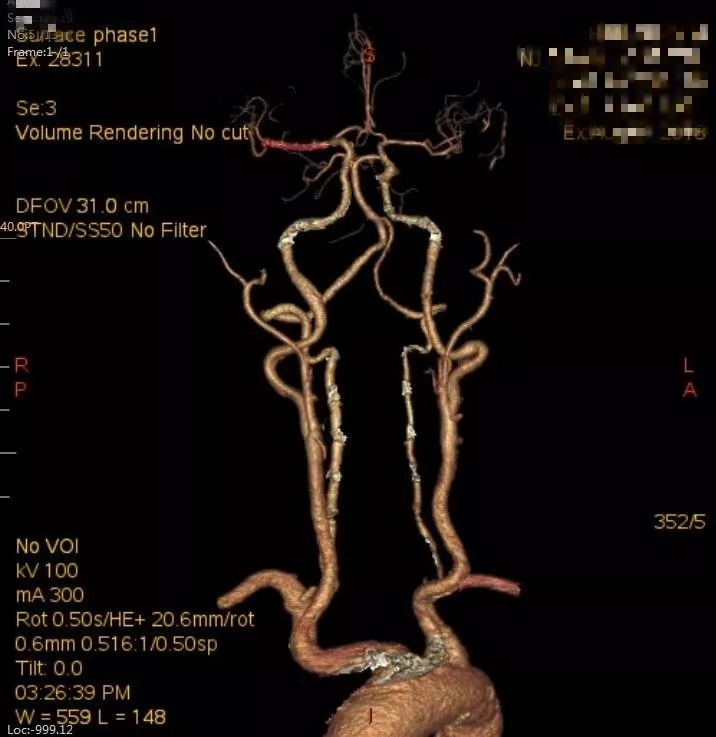

术后头颈部CTA(08-07日 17:23分)